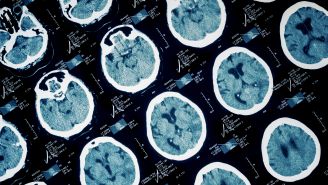

With FTD, the nerve cells in the brain’s frontal lobes (the area behind the forehead) and temporal lobes (the area behind the ears) deteriorate and shrink, which dramatically affects a person’s ability to function mentally and physically.